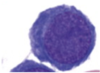

Lymphocyte